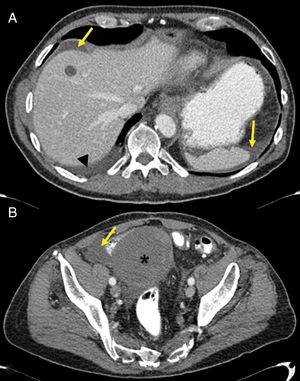

Pancreatitis (Fig. 4): pancreatitis induced by anti-angiogenic agents is rare. It tends to be mild and focal, with no fat necrosis or associated fluid collections.13 Clinical pancreatitis with no imaging findings is also possible.14

Figure 4.Pancreatitis in a 50-year-old man with stage IV renal cell carcinoma, treated with sunitinib. (A and B) Computed tomography (CT) shows densification of fat and peripancreatic fluid, as well as a small collection (arrow). No association between the pancreatitis and the drug is suspected and the patient continues on the same treatment. (C and D) CT scan of the same patient one month later, with multiple collections with air bubbles inside (arrow). On this occasion, sunitinib-induced necrotic pancreatitis is diagnosed and second-line treatment with axitinib is started.